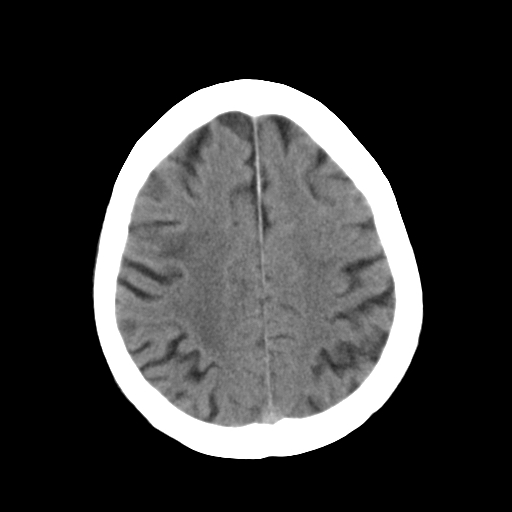

标题: CT25306:男性,75岁。右侧肢体无力一周。 [打印本页]

标题: CT25306:男性,75岁。右侧肢体无力一周。

右侧小脑楔形片状低密度影,考虑脑梗塞,建议mri或增强检查除外肿瘤占位

1)右侧小脑梗塞。2)脑萎缩。